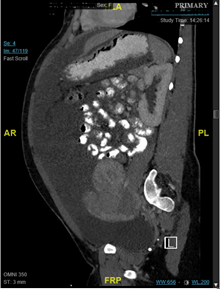

A 30-year-old nulliparous female presented to the emergency room with a chief complaint of abdominal discomfort, shortness of breath, and significant abdominal distension. On three prior occasions spanning 4 months, and prior to the Gynecology team being consulted, she was found to have severe ascites. Approximately 4 liters of benign serous fluid was drained each time via paracentesis. Cytology yielded benign pathology. She had no complaints of fevers, weight loss, or other constitutional symptoms, and had no recent travel history. She had no other significant past medical, surgical, or family history. On physical examination, she was distraught, tachypneic, and her abdominal exam showed distention, a fluid wave, and a 20-week fibroid uterus. EKG and echocardiogram were normal. Liver function and CA-125 tests were normal, and a screen for systemic lupus erythematosus was negative. Quantiferon testing was also negative. CT scan showed a large 20cm fibroid uterus and large ascites with no pleural effusion or other findings, and an MRI of the pelvis demonstrated “innumerable” uterine fibroids. It was explained to the patient that her presentation did not fit classic criteria for a specific disease, but that it could be related to her leiomyomas. After extensive counselling, she consented to an exploratory laparotomy with possible abdominal myomectomy. Intraoperatively, a complete survey showed no other abdominal pathology. 35 uterine leiomyomas were resected (largest measuring 6x5cm) and 2 liters of ascitic fluid were removed. Frozen pathology demonstrated benign leiomyomas. A JP drain was placed to monitor output. The production of peritoneal fluid was minimal during her hospital stay, and she did not re-accumulate any ascites more than one year post-operatively. The final pathology showed benign leiomyomas weighing 498g, and the abdominal fluid cytology was benign (Figure 1A) (Figure 1B).

Figure 1A CT scan showing large abdominal ascites.